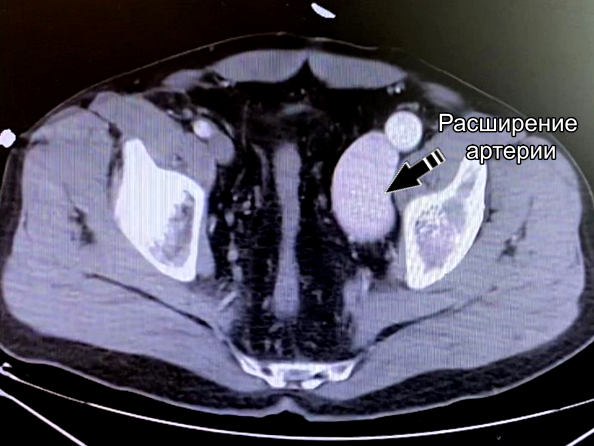

По результатам ЭХОКГ выявлена значимая перегрузка правых отделов сердца. Во время КТ ангиографии врачи обнаружили артерио-венозное соустье в области подколенной ямки (патологическое сообщение между артерией и веной, приводящее к перегрузке сердца). За годы функционирования этой артерио-венозной фистулы произошло расширение артерио-венозной стенки, что привело к значительному расширению артерии. Это грозило разрывом аорты или развитием аневризмы сердца.